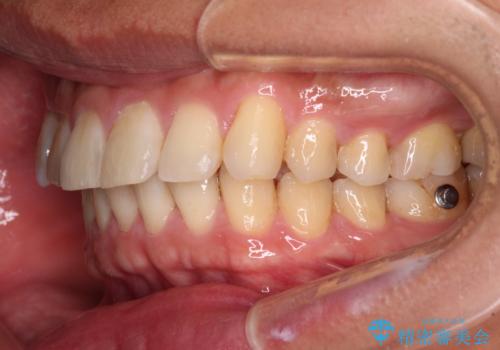

- インビザライン

- 4年8ヶ月

配属異動や長時間勤務などによりインビザラインが十分に装着できない期間があり、インビザライン有効期限5年間ギリギリとなってしまいました。